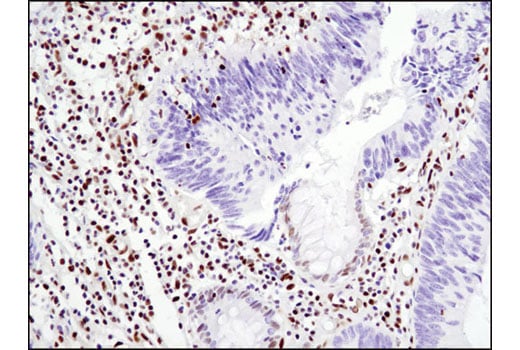

Immunohistochemical analysis of paraffin-embedded human colon carcinoma using Glucocorticoid Receptor (D6H2L) XP® Rabbit mAb.

Immunohistochemistry Image 1: Glucocorticoid Receptor (D6H2L) Rabbit Monoclonal Antibody